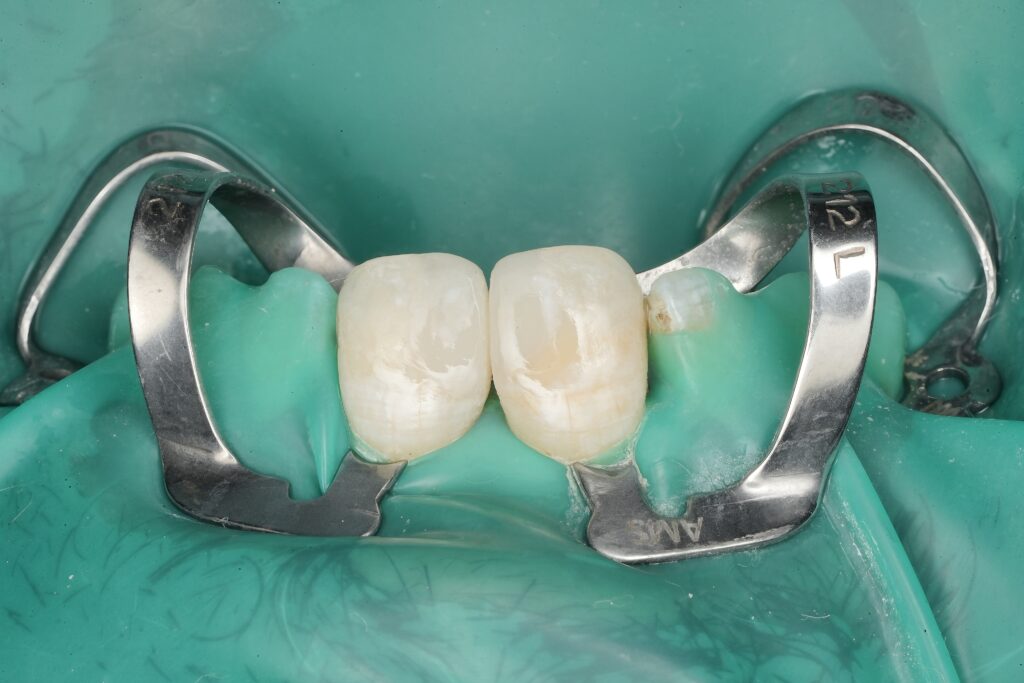

2) Rubber dam isolation (non-negotiable)

Rubber dam was placed before any definitive steps. Adhesive dentistry is moisture-sensitive; contamination reduces bond quality and increases risk of marginal staining, post-op sensitivity, and early breakdown.

Clinical tip: clamp stability + floss ligatures + teflon/caulking as needed. Your “bonding field” should look like a controlled laboratory.